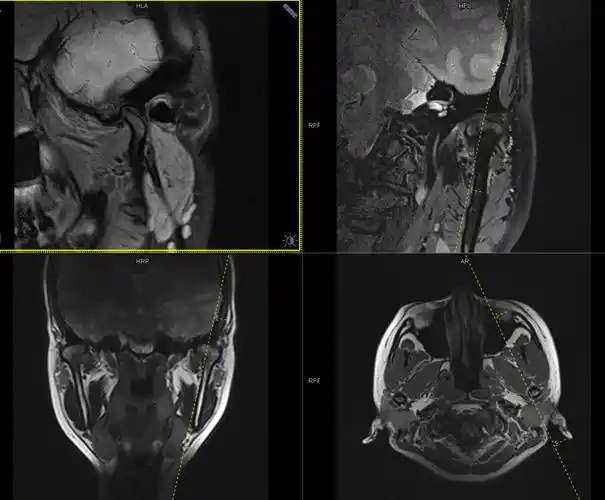

颞下颌关节紊乱的磁共振检查